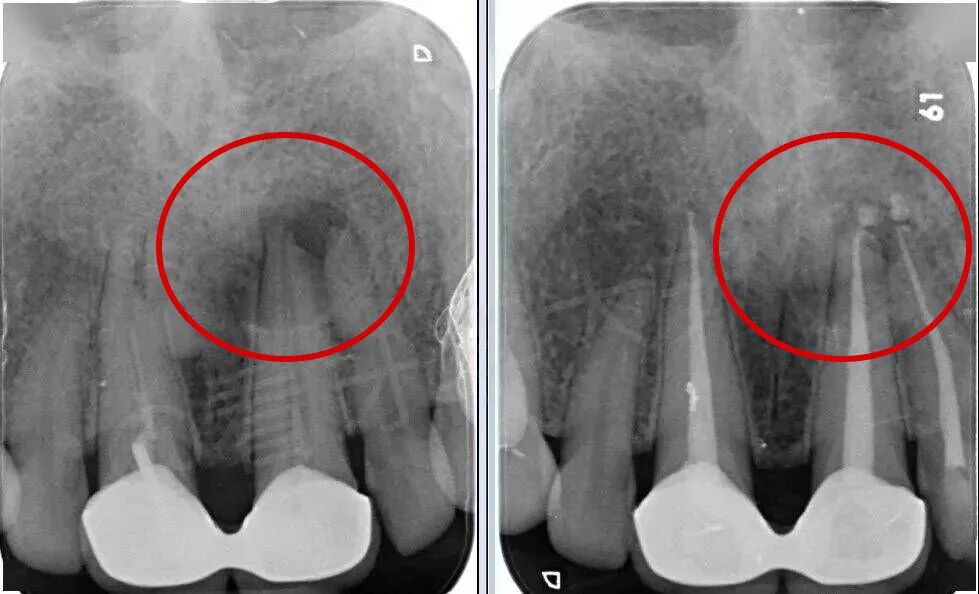

🔎根管治疗

X光拍片为什么要等看牙为什么要拍片?非专业人士如何看懂自己的牙片!_https://www.jmylbn.com_新闻资讯_第10张

△白色充填物充满整个牙根。